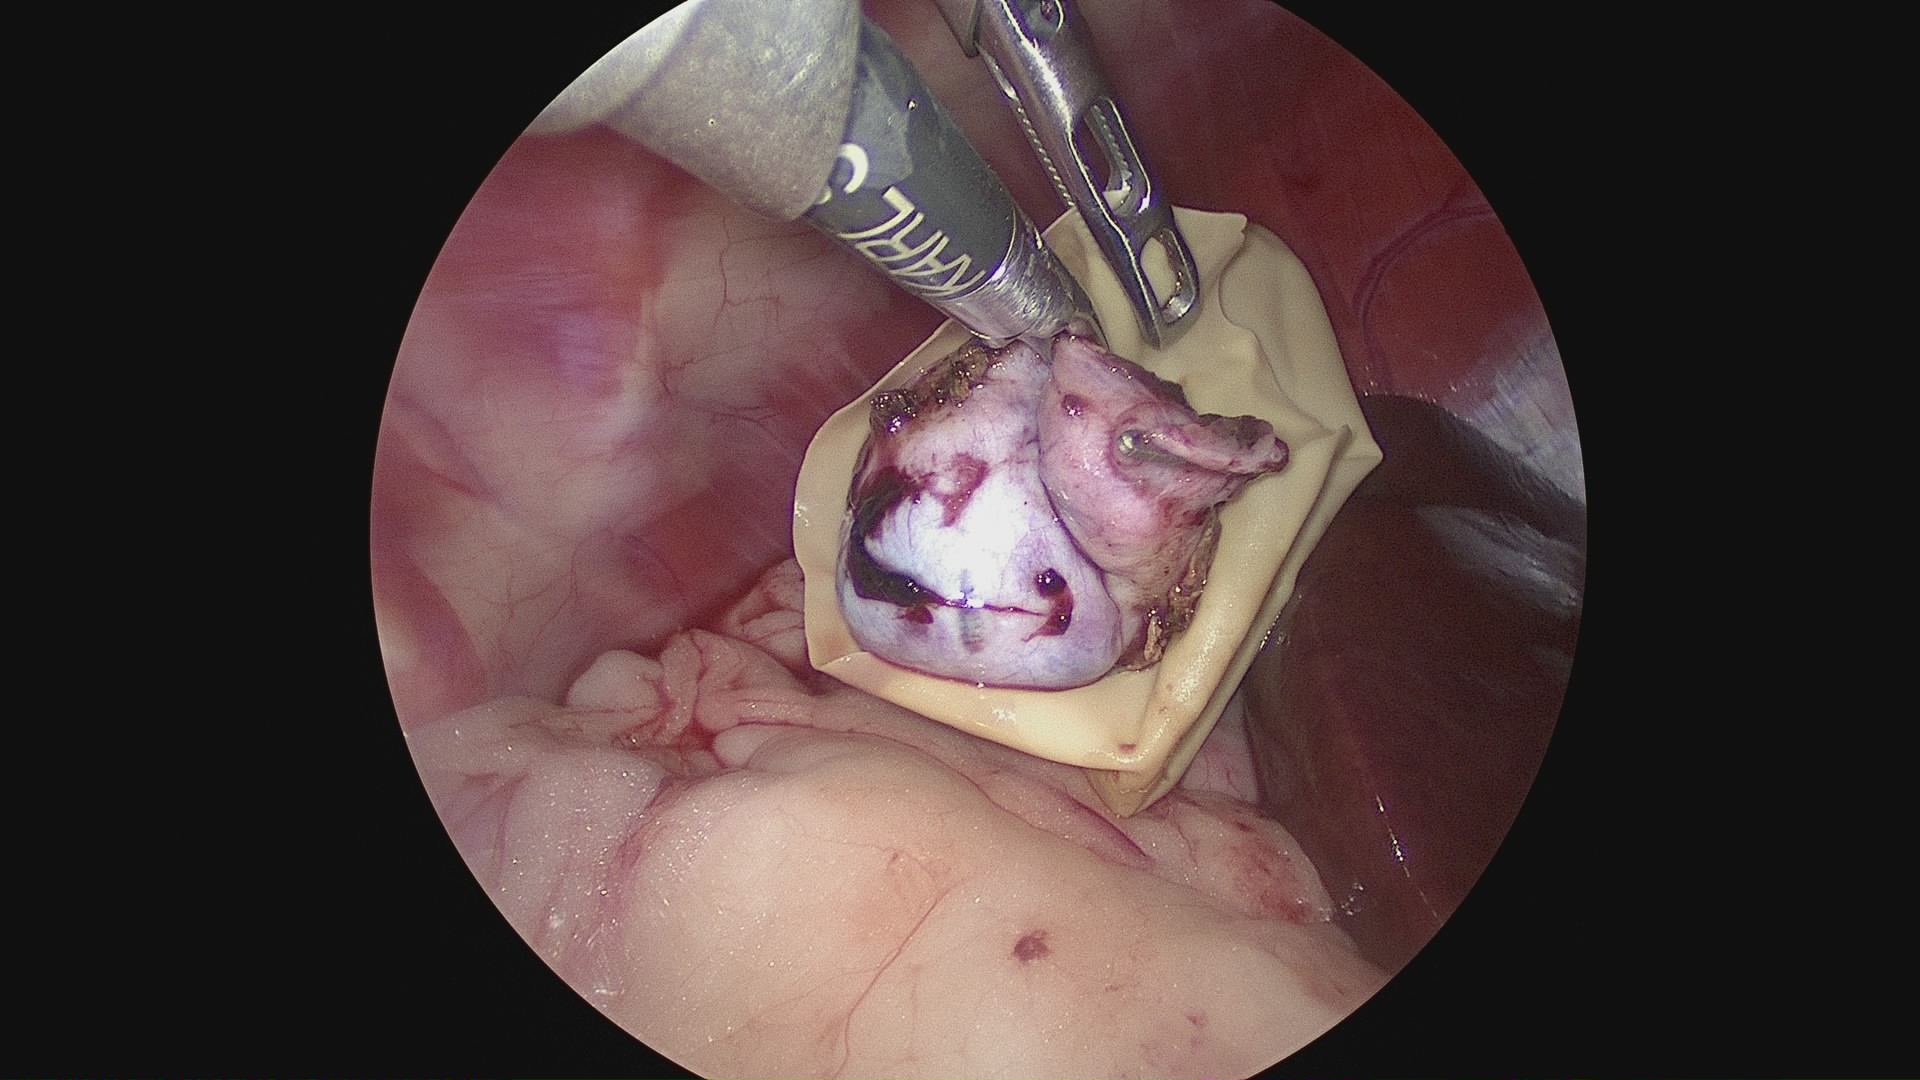

腹腔鏡下胆嚢摘出術(術中)

術前に行う超音波検査とCT造影検査により適応可能な場合は、腹腔鏡で胆嚢を摘出します